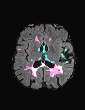

In recent years, data-driven machine learning (ML) methods have revolutionized the computer vision community by providing novel efficient solutions to many unsolved (medical) image analysis problems. However, due to the increasing privacy concerns and data fragmentation on many different sites, existing medical data are not fully utilized, thus limiting the potential of ML. Federated learning (FL) enables multiple parties to collaboratively train a ML model without exchanging local data. However, data heterogeneity (non-IID) among the distributed clients is yet a challenge. To this end, we propose a novel federated method, denoted Federated Disentanglement (FedDis), to disentangle the parameter space into shape and appearance, and only share the shape parameter with the clients. FedDis is based on the assumption that the anatomical structure in brain MRI images is similar across multiple institutions, and sharing the shape knowledge would be beneficial in anomaly detection. In this paper, we leverage healthy brain scans of 623 subjects from multiple sites with real data (OASIS, ADNI) in a privacy-preserving fashion to learn a model of normal anatomy, that allows to segment abnormal structures. We demonstrate a superior performance of FedDis on real pathological databases containing 109 subjects; two publicly available MS Lesions (MSLUB, MSISBI), and an in-house database with MS and Glioblastoma (MSI and GBI). FedDis achieved an average dice performance of 0.38, outperforming the state-of-the-art (SOTA) auto-encoder by 42% and the SOTA federated method by 11%. Further, we illustrate that FedDis learns a shape embedding that is orthogonal to the appearance and consistent under different intensity augmentations.